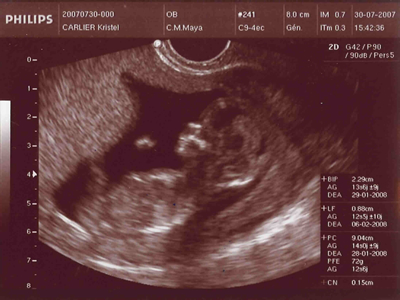

Ma première echographie...

Voici une echo révélatrice...